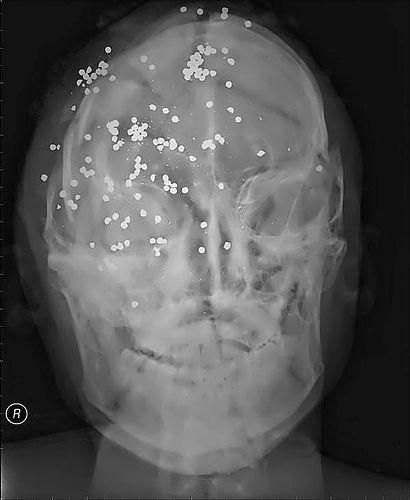

Выстрел из дробовика в голову

Выстрел в голову